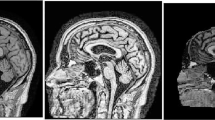

Alzheimer’s disease (AD) is a latent progressive neurodegenerative disease. Early detection can prevent further damage to patient’s health. We proposed a 3D abnormal perception depth residual network based on the squeeze and excitation module (RSE) and recurrent slice attention module (RSA). In our model, RSE captures the importance of different channels by integrating extrusion and excitation modules into residual blocks, while RSA aims to model 3D MRI images as slice sequences to capture the long-term dependence of different slices in different directions. Our model combine the context information of the abnormal area with local and spatial information. Experimental results show that the accuracy of our method is 87.5%, which is better than the most advanced model in terms of normal cognition (NC), early mild cognitive impairment (EMCI), late mild cognitive impairment (LMCI) and Alzheimer’s disease (AD) on the ADNI dataset. The CAM visualization results also show that our method can successfully highlight the most contributing regions of 3D MRI images.